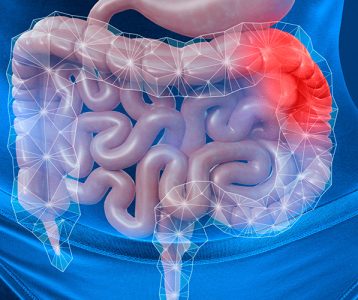

Dados da literatura sugerem que o risco de câncer colorretal está fortemente associado a fatores de estilo de vida, incluindo um componente dietético que pode ser mediado pela microbiota intestinal. Estudos recentes demonstraram, ainda, que a microbiota do cólon é alterada em pacientes com a neoplasia. Além disso, já foi comprovado que bactérias probióticas específicas modulam a inflamação e reduzem a proliferação tumoral em modelos animais de carcinogênese e podem oferecer benefícios terapêuticos para pacientes com a doença.

A microbiota tumoral foi caracterizada pelo aumento da diversidade microbiana e enriquecimento de vários táxons, incluindo Fusobacterium, Selenomonas e Peptostreptococcus – em comparação com a microbiota do grupo controle. “Pacientes com câncer de cólon que receberam probióticos tiveram uma maior abundância de bactérias produtoras de butirato, especialmente Faecalibacterium e Clostridiales spp no tumor, mucosa não tumoral e microbiota fecal”, relatam os autores. Ao mesmo tempo, os gêneros associados à neoplasia, como Fusobacterium e Peptostreptococcus, tendiam a ser reduzidos na microbiota fecal de pacientes que receberam os probióticos.

De acordo com os autores, pacientes com câncer de cólon abrigam uma assinatura de microbiota distinta no tecido tumoral e na mucosa próxima, que foi alterada com a intervenção probiótica. “Como a microbiota associada ao câncer colorretal está sendo continuamente definida à medida que novos biomarcadores da doença são descobertos, a disbiose microbiana observada em pacientes pode ser manipulada por bactérias probióticas”, acentuam.

Dessa forma, os autores afirmam que as cepas probióticas usadas no estudo se mostram promissoras como um componente benéfico do tratamento e desenvolvimento terapêutico no câncer colorretal, uma vez que a microbiota do cólon é alterada pela doença. “Nossos resultados mostram promessas de potenciais benefícios terapêuticos nessa neoplasia pela manipulação da microbiota”, argumentam. O artigo ‘Intestinal microbiota is altered in patients with colon cancer and modified by probiotic intervention’ foi publicado em 2017 no BMJ Open Gastroenterology .